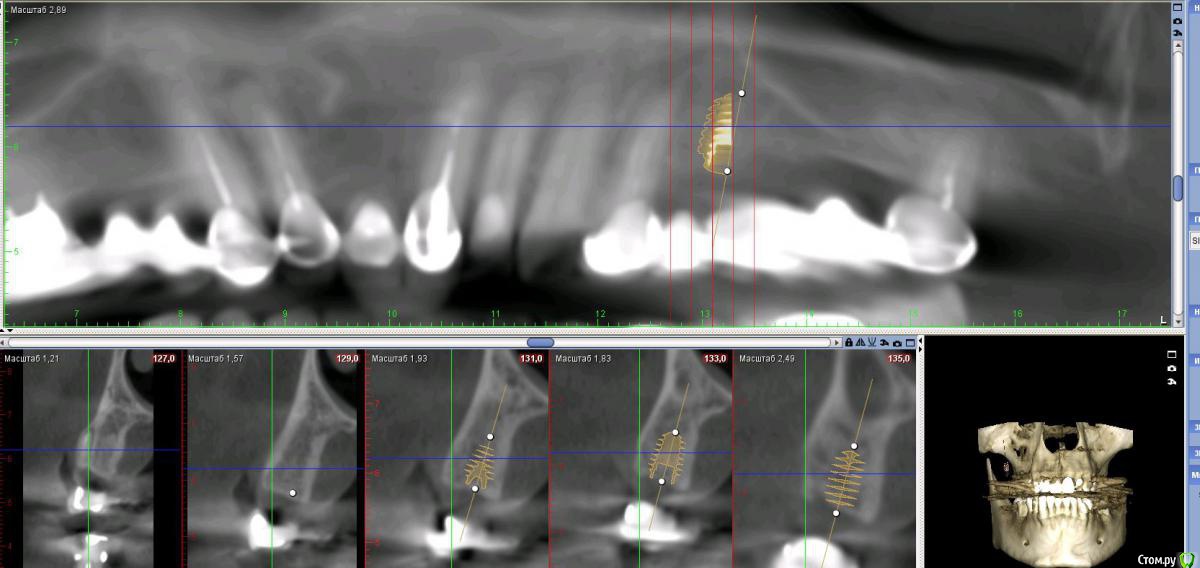

Дмитрий Л. Опубликовано 16 ноября, 2018 Поделиться Опубликовано 16 ноября, 2018 (изменено) Здравствуйте всем)Ситуация такая: старый мост 24-28. 28 симптоматичен, пациент принимает аб и противовосп. Имеется: - 24 перирадикулярные изменения (асимптомно)- 28 перирадикулярные изменения (обострение)- утолщение слизистой гайморовой (асимптомно)- невозможность имплантации в обл 26 (высота кости не позволяет) Пожелания пациента:- удаление 28 - желание сохранить мост - имплантация - нежелание носить съемную конструкцию Как планирую я:- перелечить 24, кальций 2-6 мес.- удалить 28- изготовить съёмник- выждать 4-6 мес. Повторить КТ, оценить гайморовую- имплантация 25, имплантация "где-то в обл 27" - всеми силами избежать синуса Мои грёзы:1. Ставить вблизи 24 - риск. Нужно лечить 24... реэндо... долго... может удалить? 2. Я верю, что причина хр гайморита - 28. Так ли это? Стоит ли ожидать позитивной динамики? 3. На сколько уйдёт кость после удаления 28 за 4-6 мес.? Её и так мало... Станет ли меньше? Графтить 28 не хочу. Там микробы. 4. Объём кости в обл 27-28 требует коротышку. Первыми приходят на ум Штрауман 6 мм (4 мм в кости, станет красиво) или ЭниРидж (бикортакально, скорее всего в пазуху на 1-2 мм). Нюанс в том, что я не работал этими системами... И коротышки не ставил. В общем придётся искать наборы, но это мои проблемы. 5. Итоговая конструкция: мост 25-27. При чём 27 имеет длину 4-6 мм, не слишком ли короткая дистальная опора? Вот спланировал приблизительно так... Надеюсь на отклик. Изменено 16 ноября, 2018 пользователем Дмитрий Л. Ссылка на комментарий

Neilrus Опубликовано 16 ноября, 2018 Поделиться Опубликовано 16 ноября, 2018 У эниридж есть совсем коротыши 5,5х5, для семерки, если не хотите лезть в синус самое то, у него огромная площадь получается за счет особенностей резьбы. Только для него набор специальный с ограничителями должен быть, но дилер может и даст в аренду за имплантат, покупать его не вижу смысла, нужен раз в полгода 1 Ссылка на комментарий

Nazim_NV86 Опубликовано 16 ноября, 2018 Поделиться Опубликовано 16 ноября, 2018 В районе 28 пока перфа зарастёт пройдет немало месяцев. Пока вырастет кортикалка. Толщина кости к этому времени станет вдвое меньше. А до этого закрытым методом поднять мембрану более 1мм будет непросто. Просто мысли.. 1 Ссылка на комментарий